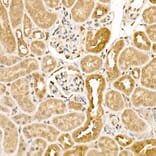

Anti-CK1 epsilon Antibody (A305708)

Rabbit polyclonal antibody to CK1 epsilon for IHC.

Applications

IHC

IHC: 1:50-1:200